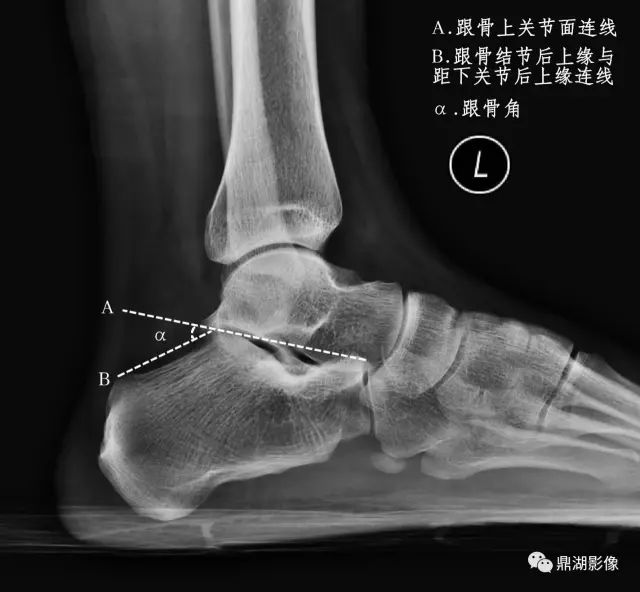

影像检查

辅助检查方法主要是X线检查,应负重条件下摄足正侧位X线片,主要在足侧位片测量足弓的角度改变。